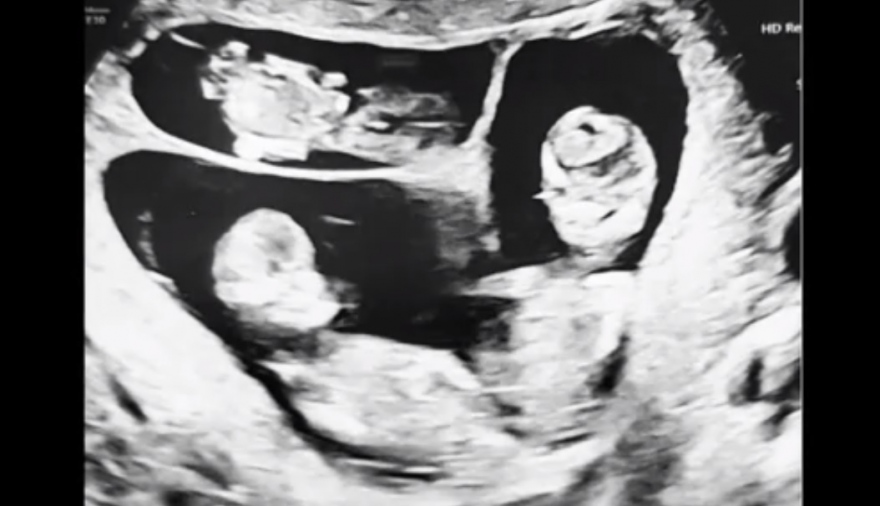

Ritka eset: hármasikreket vár a hármasiker anyuka

Ez a helyzet a világon is nagyon ritka! Judit, a Norvégiában élő kismama most hazalátogatott, és mesélt különleges terhessége időszakáról a Fókusz stábjának, de megszólal édesanyja is, aki szintén átélt már hasonlót.